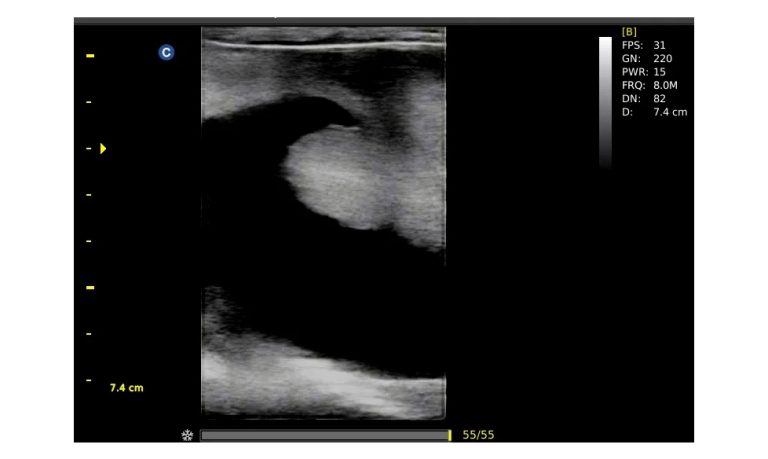

Ultrasound

Wide range of Ultrasound machines that suites a variety of applications from abdominal to rectal scans, we take in consideration how the world is moving towards mobility and mobile applications.

SonoScape Pro Pet E11

Smart Imaging

Introducing the first portable ultrasound with the C-Field+TM platform, redefining diagnostic imaging. Designed for veterinarians, it delivers unmatched clarity, ultra-fast processing, and seamless adaptability for all species. Experience Smart Imaging, Heartfelt Care—anywhere.

Equipped with cutting-edge veterinary software and optimized workflows, it embodies our commitment to Smart Imaging, Heartfelt Care – Wherever Their Journey Leads, with unparalleled performance and adaptability, this innovative system empowers veterinarians to provide exceptional care across all diagnostic applications,

Esaote MyLab Sigma; So Fast, So Easy

Esaote’s new MyLab™SigmaVET is the smart, portable solution that allows use of an ultrasound whenever a quick and complete diagnosis is required.

EBIT50/60 VET

All the power you need

The EBit provides all the power you need for today´s challenging clinical environment, yet remain ultra-portable, ultra-affordable. With its cutting-edge imaging technologies, precise and intuitive workflow, ergonomic and eco-friendly design, versatile transducers for all applications from top to toe, we firmly believe the EBit to be the very best portable ultrasound in its class today.

ECO5 VET

Ultra-Portable, Ultra- Affordable, Color doppler

The multi-purpose user presets, comprehensive measurement & report system, built-in EasyView image achieve system, quick image storage / retrieve / transfer, one-button direct print, make the complete workflow better than what you can dream of.